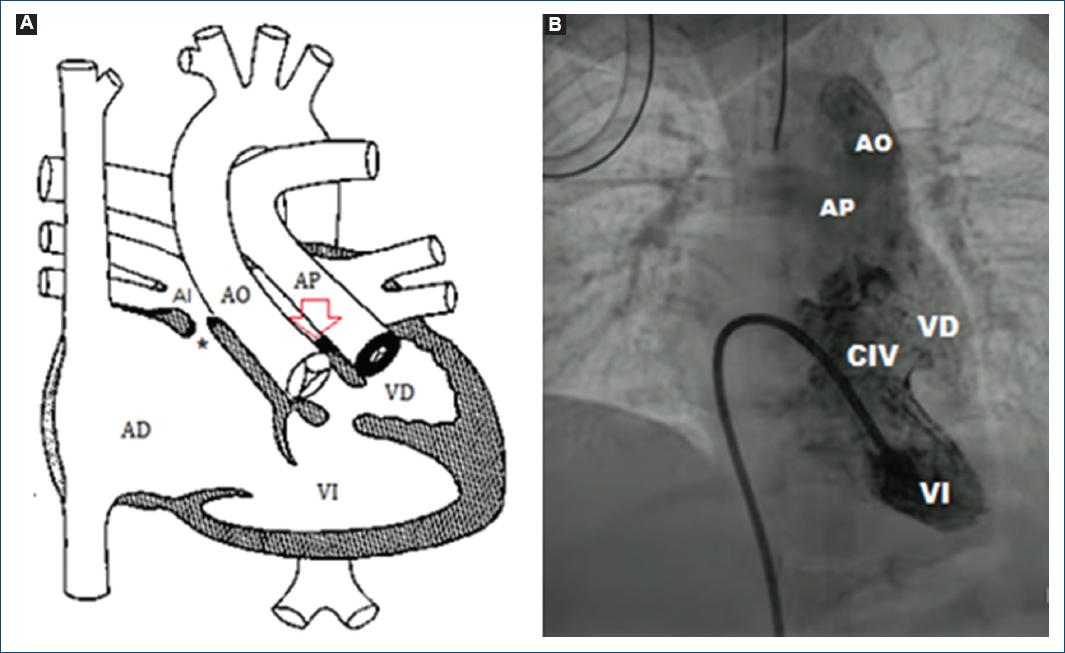

La radiografía mostró mesocardia con levoápex, con hipertensión venocapilar (Fig. 1). Se realizaron ecocardiograma transtorácico y cateterismo cardíaco, los cuales concluyen situs solitus atrial y abdominal, mesocardia con dextroápex, retornos venosos sistémicos y pulmonares lateralizados, conexión atrioventricular de tipo discordante y modo imperforado por ausencia de conexión atrioventricular izquierda, atresia tricuspídea e inversión ventricular (topología de mano izquierda) con las siguientes características: defecto interatrial pequeño y restrictivo con gradiente medio de 10 mmHg (Fig. 2); conexión ventriculoarterial tipo doble vía de salida del ventrículo derecho (rudimentario) modo perforado con aorta anterior e izquierda y doble infundíbulo, válvula pulmonar bivalva y displásica sin estenosis pulmonar; comunicación interventricular de entrada con extensión a la salida no obstructiva (Fig. 3), conducto arterioso persistente, disfunción diastólica del ventrículo sistémico y función sistólica conservada.

Figura 3 A: diagrama de Mullins que representa la discordancia atrioventricular por inversión ventricular (topología de mano izquierda), ausencia de conexión atrioventricular izquierda (atresia tricúspidea) con doble salida del ventrículo derecho (VD) rudimentario con doble infundíbulo y estenosis pulmonar. La flecha señala el piso fibromuscular de la atresia tricuspídea. B: ventriculografía que muestra el ventrículo izquierdo (VI), una comunicación interventricular (CIV) amplia y el VD rudimentario, de donde emergen dos vasos sistémicos: la arteria aorta (AO) y la arteria pulmonar (AP). AD: atrio derecho; AI: atrio izquierdo (video para la imagen 2: https://youtube.com/shorts/RIO17heO154?feature=share).